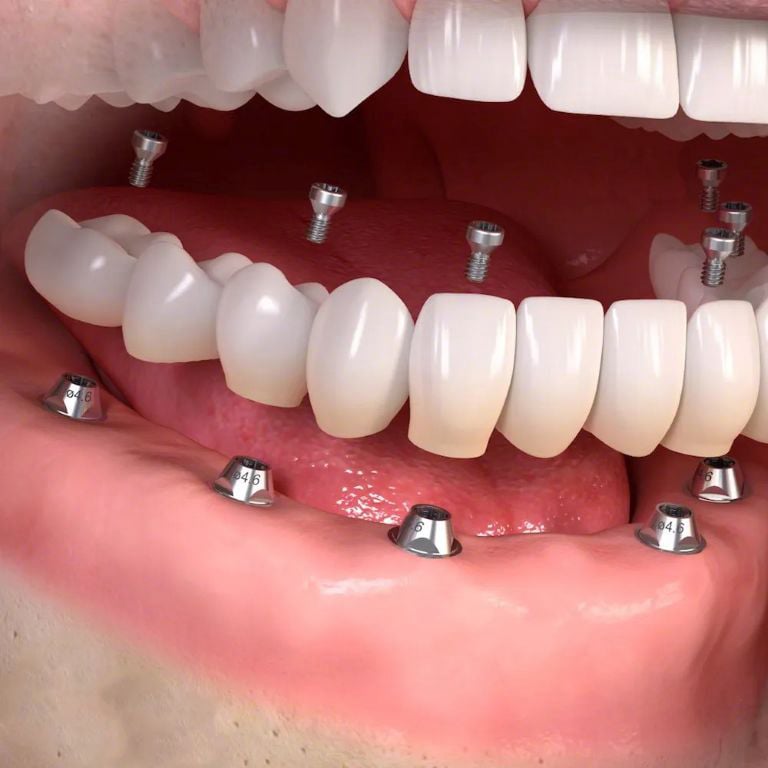

¿Buscas una solucion fija duradera?

Los implantes dentales permiten recuperar función y estética de forma estable y segura.